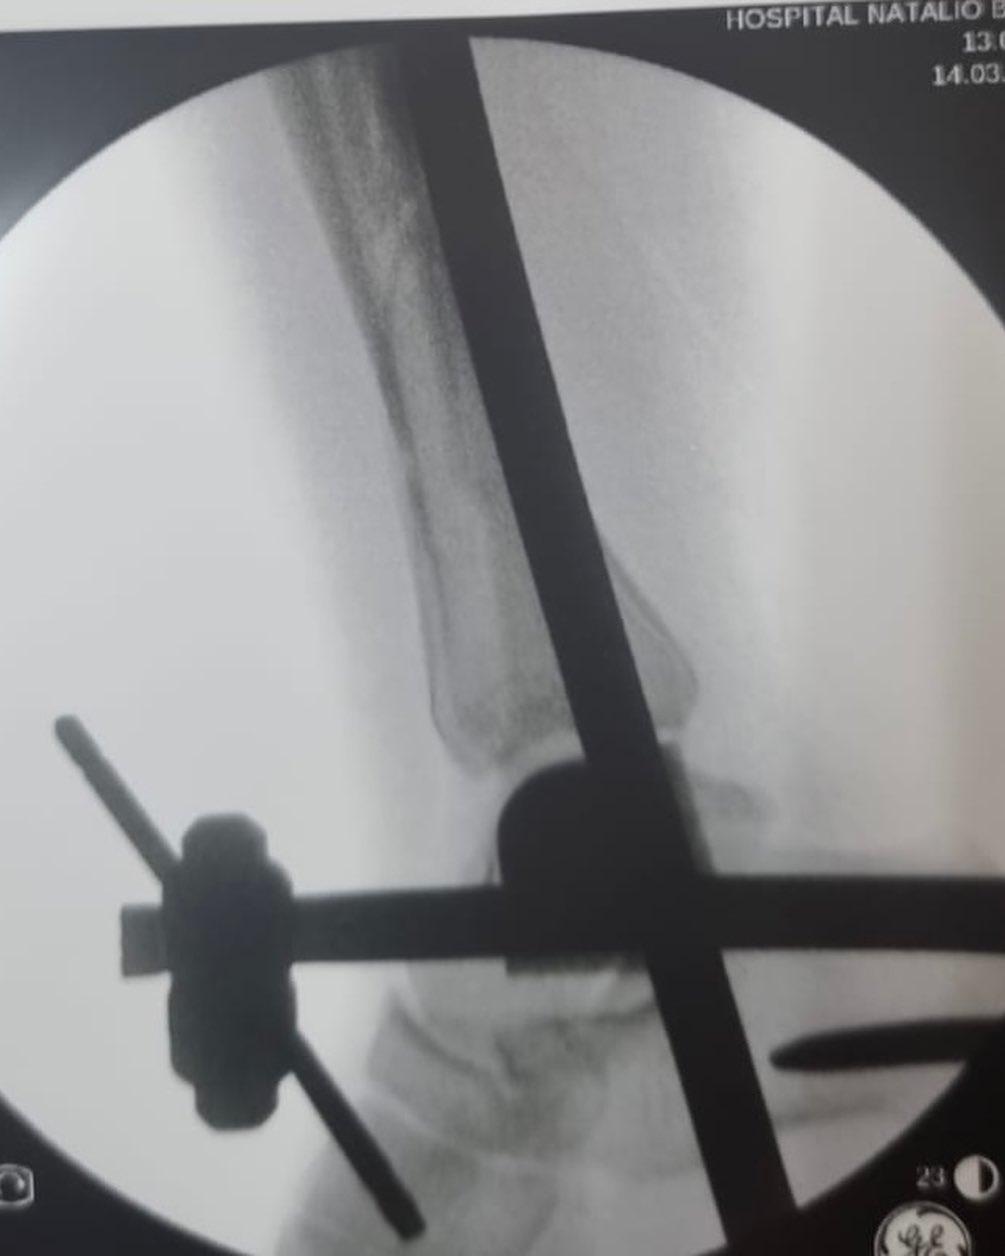

El manejo inicial de una fractura compleja de tibia representa un punto de inflexión en el proceso de recuperación del paciente. Tal como lo destacó el Dr. Escobar, la fijación externa emerge como una herramienta invaluable en esta etapa crítica.

- Versatilidad: La fijación externa puede adaptarse a una amplia variedad de fracturas, permitiendo modular la carga y el movimiento según las necesidades del paciente.

La elección del tipo de fijador externo y el protocolo de tratamiento dependerán de diversos factores, como la localización y gravedad de la fractura, el estado de las partes blandas y las condiciones generales del paciente. Es fundamental que la decisión sea tomada de manera multidisciplinaria, involucrando al traumatólogo, el cirujano ortopédico y otros especialistas según sea necesario.

En conclusión, la fijación externa representa una herramienta esencial en el manejo inicial de las fracturas complejas de tibia. Al proporcionar una estabilización inmediata, facilitar la cirugía definitiva y mejorar el pronóstico funcional, esta técnica contribuye significativamente a la recuperación del paciente.